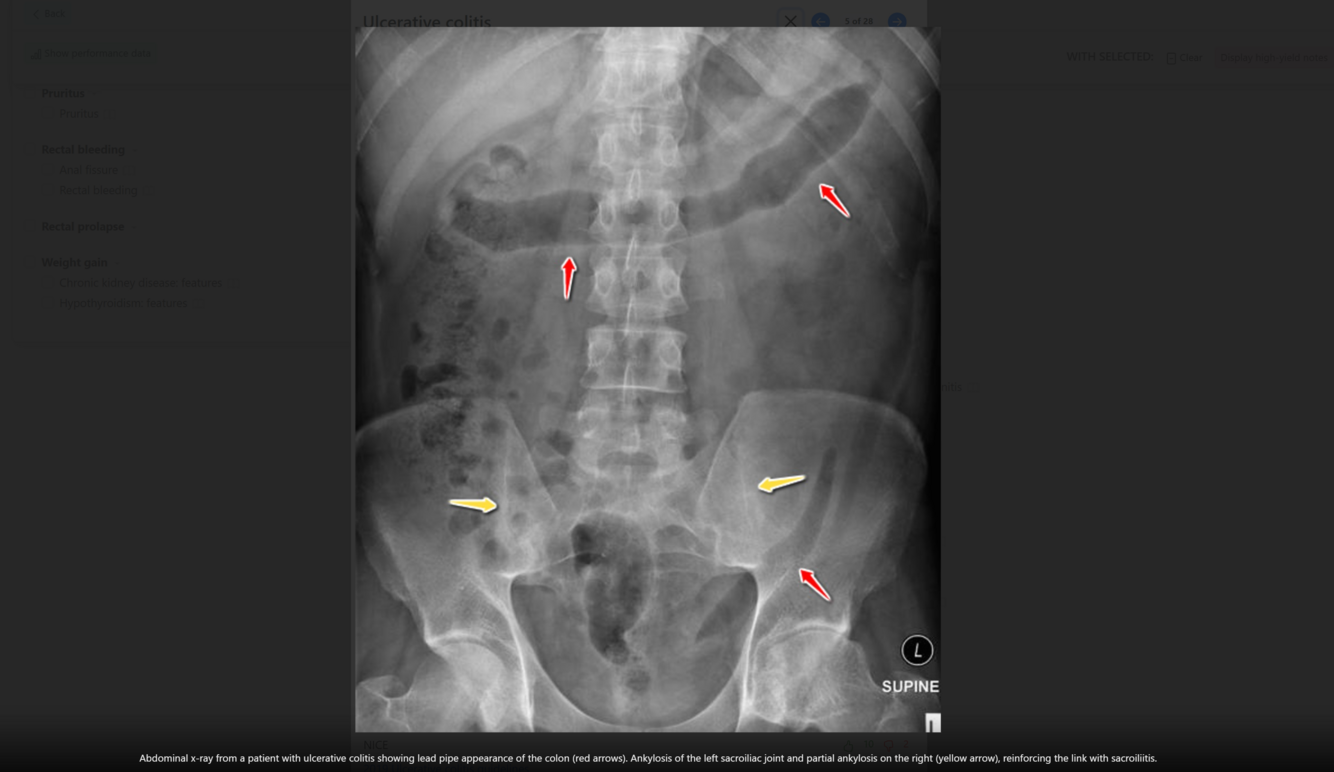

A